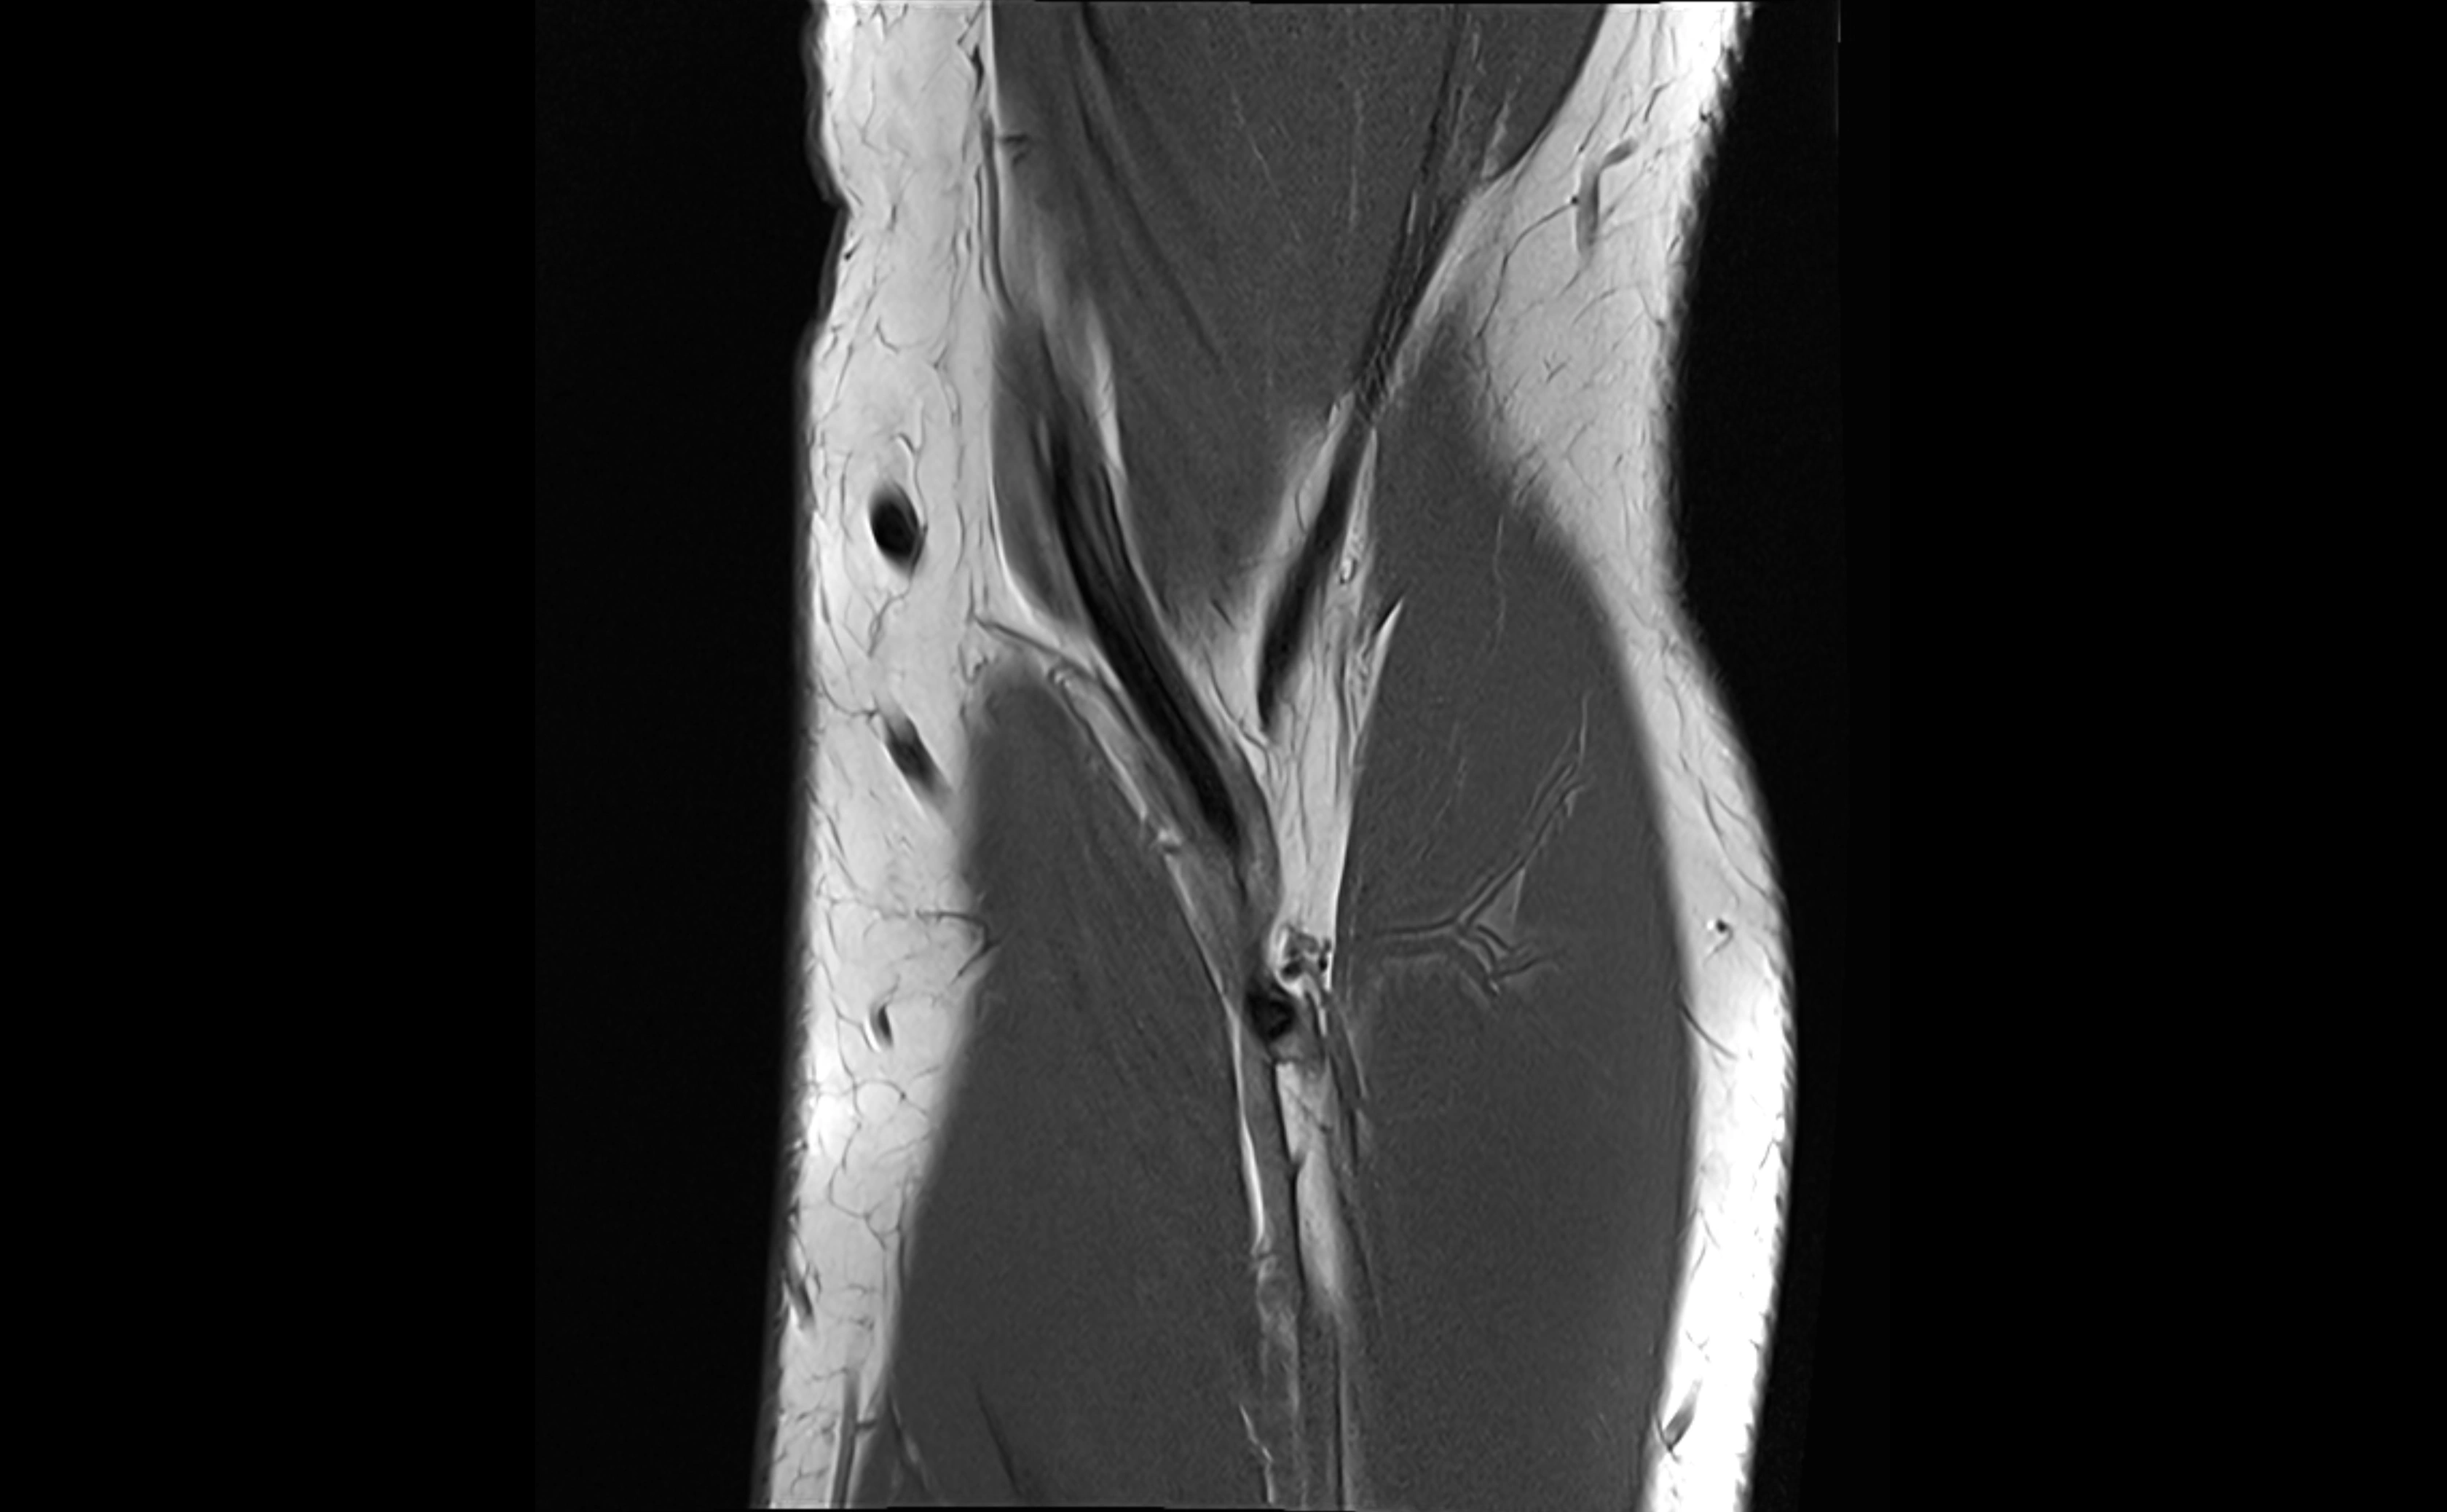

MRI Appearance

T1-weighted images:

• Ligament: low signal intensity (dark), appearing as a continuous band around the radial head.

• Adjacent fat and marrow: bright, creating contrast with the ligament.

• Thickening or disruption indicates injury or fibrosis.

• Joint capsule and synovium seen as thin low-signal lines contiguous with ligament margins.

T2-weighted images:

• Ligament: low signal (dark) with clear delineation from joint fluid.

• Fluid or edema: bright hyperintense, separating or surrounding the ligament in partial tears.

• Complete tear: discontinuity or non-visualization of ligament fibers, often with joint effusion.

STIR:

• Normal ligament: dark band encircling radial head.

• Pathology: bright hyperintense periligamentous signal suggesting edema, sprain, or partial tear.

Proton Density Fat-Saturated (PD FS):

• Normal: dark, well-defined band outlining the radial head.

• Partial tear: irregular or bright hyperintense signal within or adjacent to ligament fibers.

• Joint effusion and reactive synovitis appear bright and are well visualized.

T1 Fat-Sat Post-Contrast:

• Normal: minimal enhancement.

• Inflamed or injured ligament: focal or diffuse enhancement.

• Synovial enhancement in chronic instability or post-surgical changes.

MRI images

image